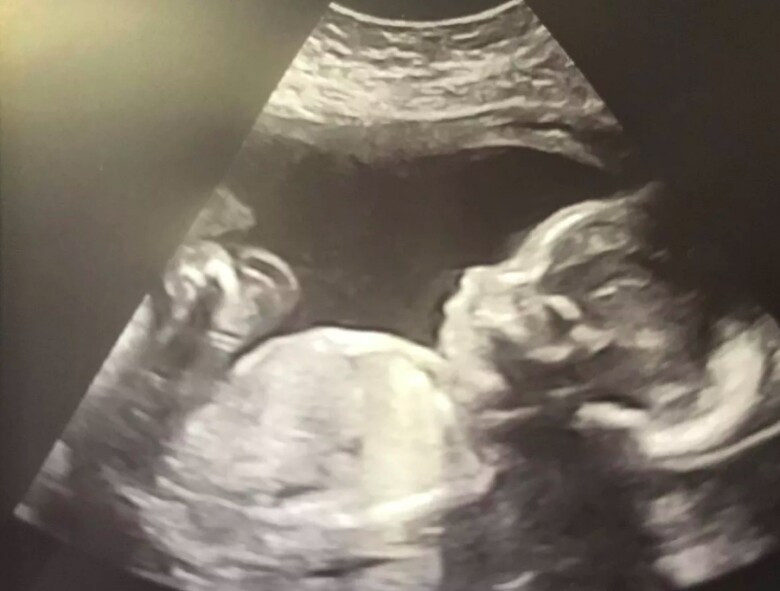

Hình ảnh siêu âm của em bé kỳ diệu Ethel.